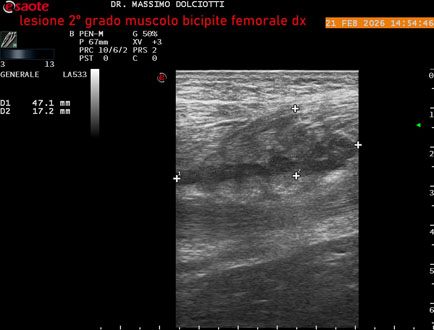

Ecografia del: 21/02/2026

Strumento: Esaote MyLab Eight

Sonda: Lineare Multifrequenza 3-13 MHz

Età Paziente: M 49 anni

Motivazione dell'esame: da 10 giorni dolore insorto durante la corsa.

Commento all'esame: le immagini ed il video documentano, al muscolo bicipite femorale destro, in sede prossimale, area disomogenea, ipoecogena, delle dimensioni di 27 x 24 mm (misura ottenuta per asse corto o trasversale) e delle dimensioni di 51 x 33 mm (misura ottenuta per asse lungo o longitudinale), da ricondurre a lesione muscolare di 2° grado con modica raccolta sieroematica intramuscolare.

Conclusioni: lesione di 2° grado al muscolo bicipite femorale destro (grade 2 injury to the right biceps femoris muscle).